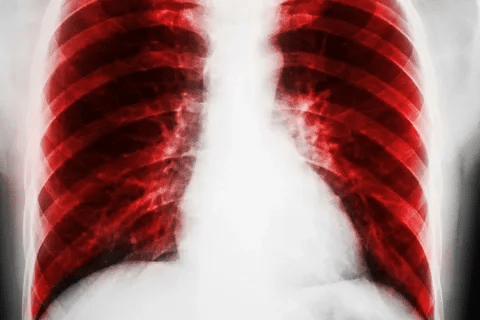

To diagnose pneumococcal pneumonia, doctors use physical exams, chest X-rays, and lab tests. Treatment usually involves antibiotics. The type of antibiotic depends on the infection’s severity and the patient’s health.